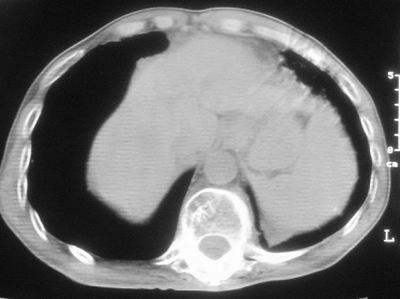

标题: CT11864:男,47岁,反复咳嗽、咯痰、咯血3年,请分析. [打印本页]

患者,男,47岁,反复咳嗽、咯痰、咯血3年,再发5天。痰培养未找到真菌、抗酸杆菌、癌细胞。

左肺上叶体积明显缩小,其内见多发透光区,纵隔向左侧移位,左肺下叶多发班片状病灶,边界模糊,1左肺上叶先天肺发育不全,2左肺下叶肺炎,

左肺上叶结核伴肺纤维化,纵隔移位,左肺下叶感染性病变,建议抗炎抗结核后复查,双肺气肿.

以下是引用xulianj在2008-2-25 21:01:00的发言:[br]左肺上叶结核伴肺纤维化有霉菌球形成,纵隔移位,左肺下叶感染性病变,建议抗炎抗结核后复查,双肺气肿.

考虑:左肺慢纤伴霉菌球形成、双肺全小叶型肺气肿。

1)考虑为:左肺上叶肺结核(空洞形成),伴左下肺感染;不排除霉菌感染可能。2)肺气肿。

左肺上叶结核伴肺纤维化空洞形成并左肺下叶感染,纵隔牵拉移位,建议作进一步检查排除左侧肺霉菌感染可能。